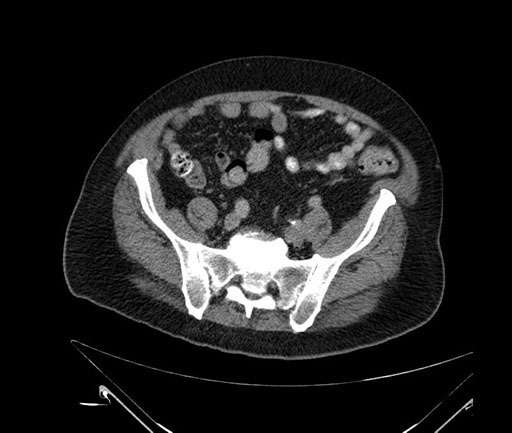

Imaging Analysis

Look through the patient's CT scan to identify any areas of concern for the necessary procedure.

Based on your CT findings, which issue(s) would give reason for "planned slowing down moment(s)" in this case?

Considering a standard Whipple procedure, what step(s) of the operation would you do differently in this case?